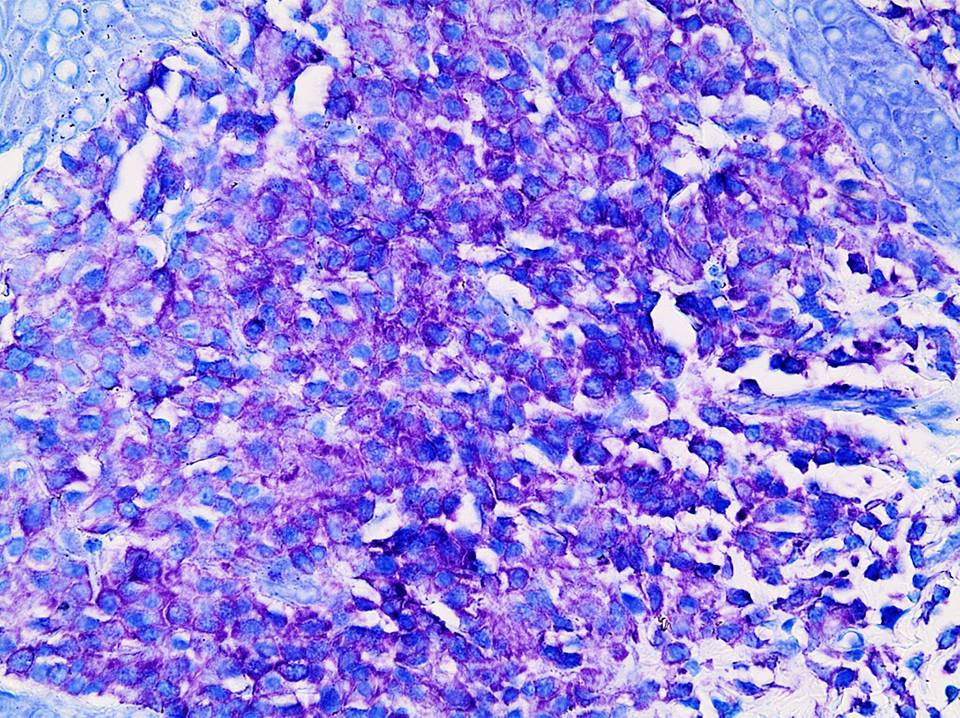

Microscopic (histologic) description

- Within the macules and plaque, mast cells are predominantly in papillary dermis

- Mast cells are round or spindle shaped with abundant eosinophilic cytoplasm, distinct cytoplasmic boundaries, large pale nuclei

- Eosinophils are often present

- Also edema of papillary dermis, subepidermal vesiculation

Microscopic (histologic) images

Positive stains

- Toluidine blue and Giemsa demonstrate metachromasia (granules are purple red)